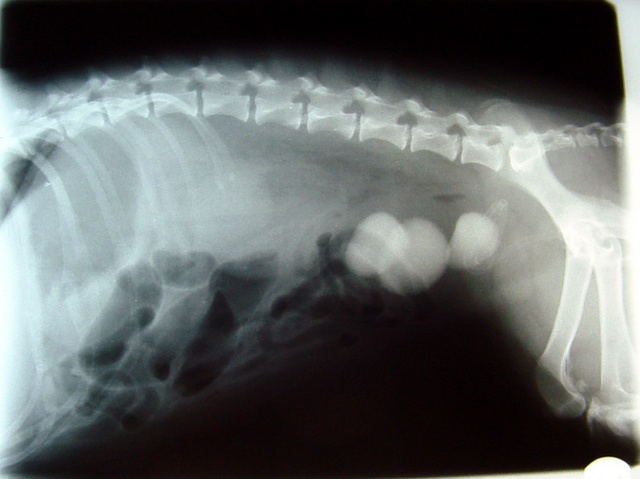

In some bladder infections, minerals in the urine crystallize and form bladder stones, which can be as small as grains of sand or larger than marbles or small rocks. Â

| X-ray of bladder stones. Image: Little Critters Vet |

Bladder stones can also create areas where bacteria can hide from antibiotics, leading to long-term infections that are difficult to treat.

Your veterinarian may be able to feel stones by palpating the bladder (ie, feeling it through the abdominal wall), but an x-ray or ultrasound is usually needed for a definite diagnosis.